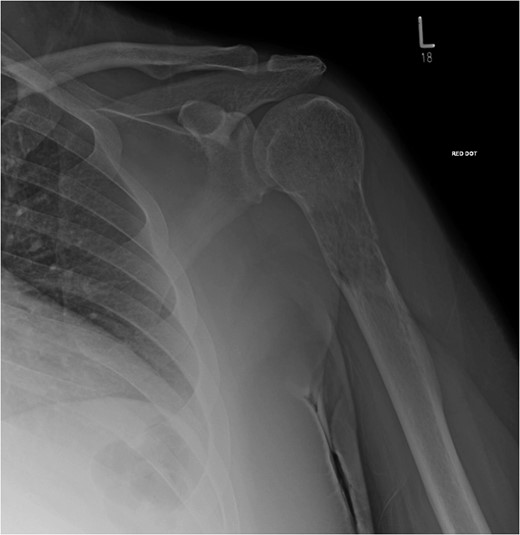

X-ray showed lytic lesion and pathological fracture of left proximal humerus. Plain radiographs of the left.